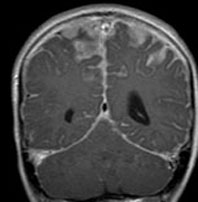

水頭症とけいれん発作で発症した例

年長児例でけいれん発作と水頭症で発症した子どもです。中央の画像に見えるように,脳幹部の周囲が線状に白く増強されています。頭頂部にはゴロンとした腫瘤形成があり,これは悪性黒色腫 メラノーマだと考えられます。